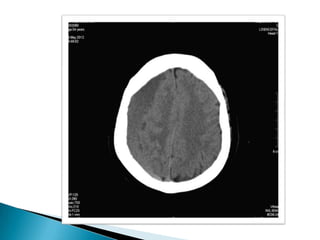

Paciente masculino de33 años de edad que ingresa en el día 13-07-12 guardia del Nombre: Marcelo Blaszczyszyn presentando traumatismo craneoencefálico provocado por caída de un tercer piso. Al momento del examen presenta Glasgow3- 15 HTO 18,9 % HB 6 Plaquetas 66

TC cerebro: Presencia de trazo fracturario a nivel occipital, temporo-parietal izquierda y hundimiento de región derecha.  Imagen hiperdensa en región fronto- temporo-parietal izquierda, con desplazamiento de la línea media y borramiento de ventrículos laterales compatible con hemorragia subdural.  Hiperdensidad compatible con hemorragia subaracnoidea.  Cefalohematoma que recorre toda la zona occipital y temporal